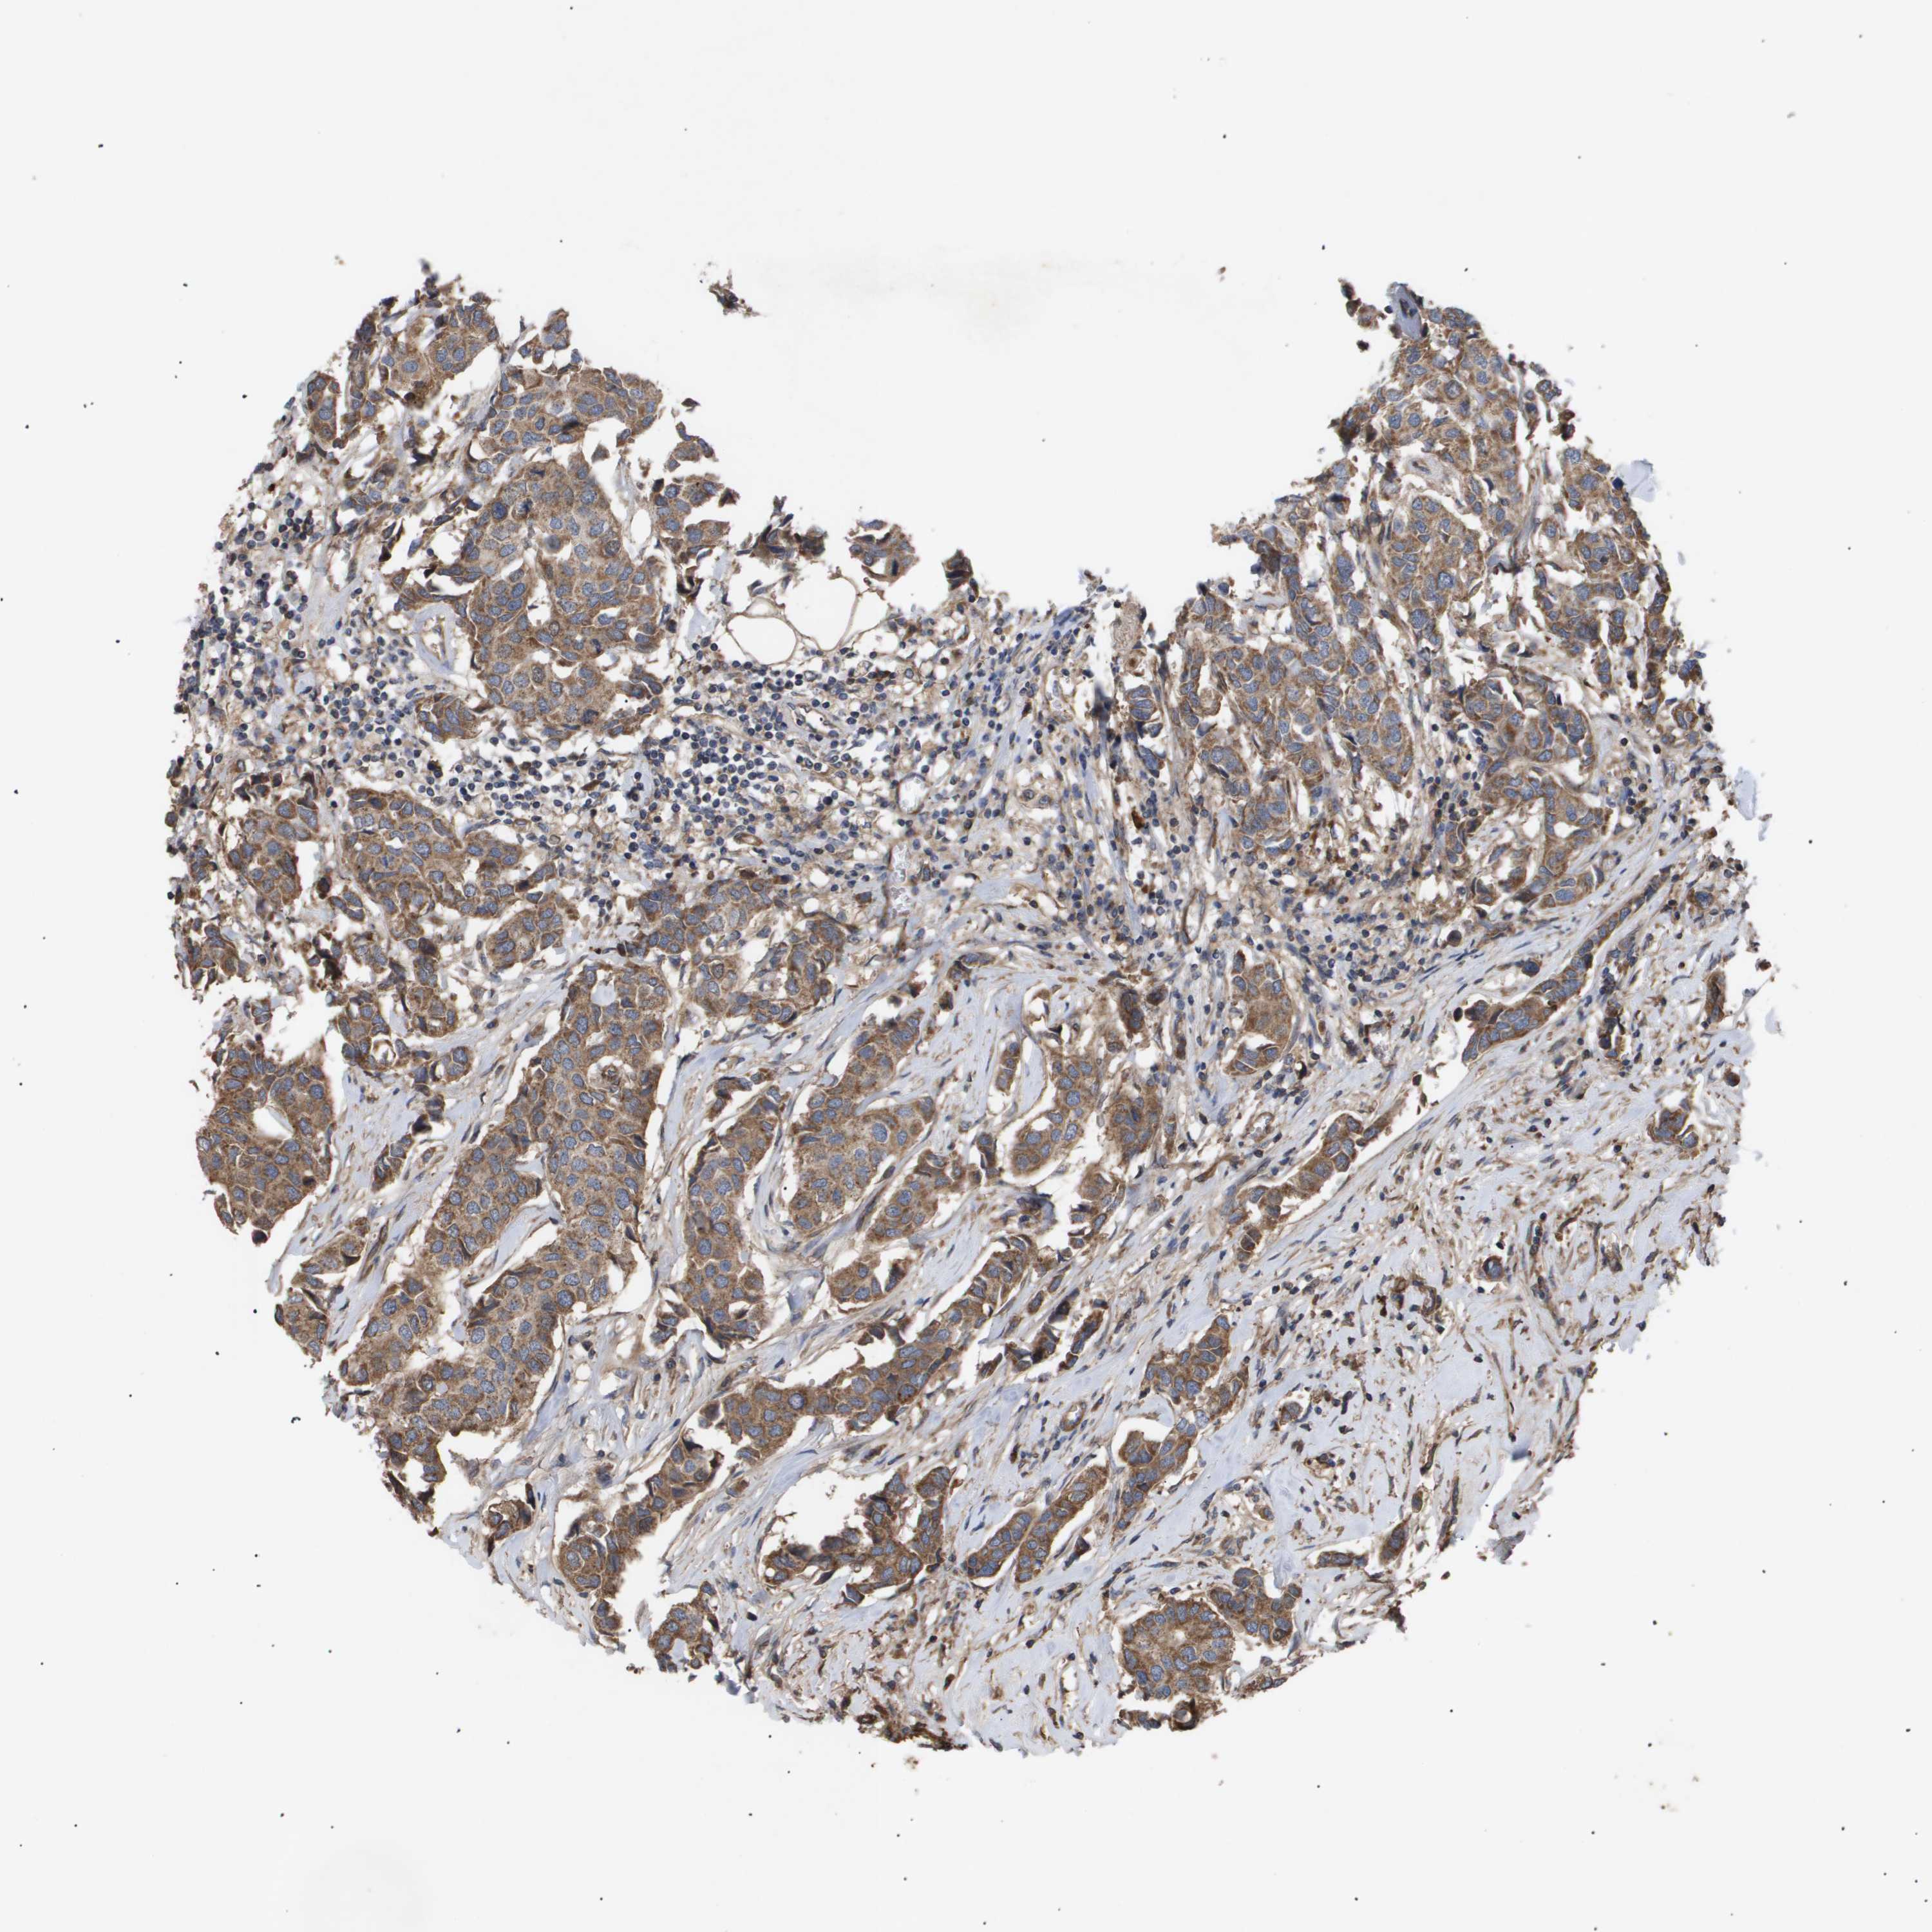

CANCER BREAST CANCER Show tissue menu

BRCA TCGA BRCA VALIDATION PROTEIN EXPRESSION